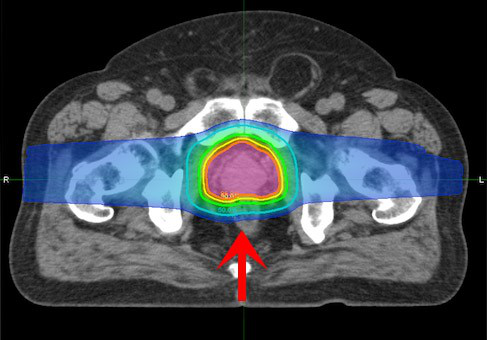

全部17例患者均接受了三维双散射保形质子治疗(3DCPT),每周连续进行5次,每次1.8 Gy相对生物合适性(RBE)。对于每位患者,将术前和术后的治疗计划MRI共同登记到治疗计划CT中。目标体积定义为术前和术后肿瘤总体积,临床目标体积(CTV)在总肿瘤体积的基础上增加5毫米的余量,以说明肿瘤扩散。规划目标体积(PTV)被定义为具有3mm额外裕量的CTV。使用了两个3场光束布置-莫霍克(图1A)或2个横向倾斜,上前斜向布置(图1B)。光束整形孔径是根据PTV投影在光束视线中约5至7 mm的定制扩展设计的。定制的光束补偿器经过单独设计,可以大水平地提高剂量的一致性,并减少组织异质性对剂量分布的影响。总剂量为45至50.4 Gy(RBE)(中位数为45 Gy [RBE])。计划被规范化,以使99%的CTV被处方覆盖,这几乎总是意味着95%的PTV接受了95%的处方计量。

左:标准放疗 右:质子治疗